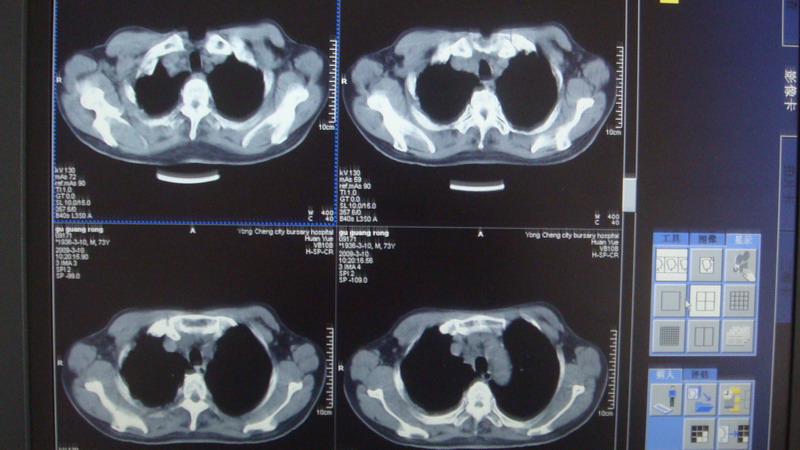

以下是引用光影相伴在2009-3-11 17:27:00的发言:[br]支持 右肺下叶周围型肺癌伴右肺门纵隔淋巴结转移;右上肺继发型肺结核(硬结\\纤维灶);右侧少量胸胸腔积液。另:不排除右侧胸膜转移可能。

以下是引用随光逐影在2009-3-11 16:57:00的发言:[br]支持 右肺下叶周围型肺癌伴右肺门纵隔淋巴结转移;右上肺继发型肺结核(硬结\\纤维灶);右侧少量胸胸腔积液。另:不排除右侧胸膜转移可能。

以下是引用草之原在2009-3-11 19:03:00的发言:[br]支持 右肺下叶周围型肺癌伴右肺门纵隔淋巴结转移;右上肺继发型肺结核(硬结\\纤维灶);右侧少量胸胸腔积液。另:不排除右侧胸膜转移可能。